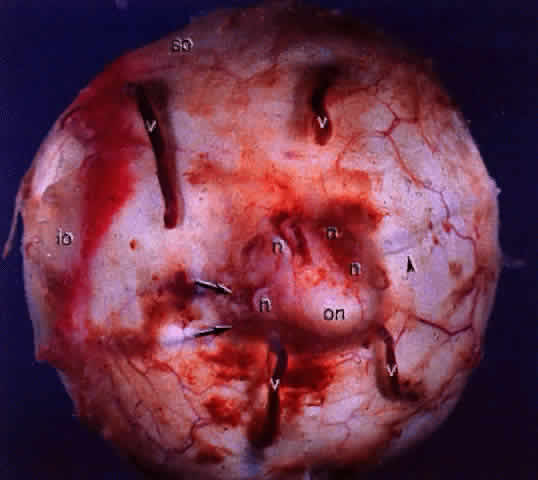

Fig. 14. Gross specimen of posterior of globe shows many of the structures shown in Fig. 13: vortex veins (v), optic nerve (on), muscular tendon of inferior oblique (io), tendon of superior oblique (so), short posterior ciliary arteries (arrows), short posterior ciliary nerves (n), and long posterior ciliary artery and nerve (arrowhead).

Fig. 13. Drawing of gross specimen of posterior of left globe, showing optic nerve surrounded by short posterior ciliary arteries (SPCAs). Wreath of short posterior ciliary nerves (lighter structures) is prominent superiorly and inferiorly. An occasional SPCA accompanies nerves. Temporal (left of optic nerve) and nasal (right of optic nerve) canals of long posterior arteries and nerves mark the horizontal meridian of the globe. Muscular tendon of inferior oblique muscle (far left) partially covers canal of long temporal posterior ciliary artery and nerve. Emissary canals of the four vortex veins lie in the oblique quadrants. Tendon of superior oblique muscle inserts superiorly, just anterior to superior temporal vortex vein. (Courtesy of Stephen Gordon)